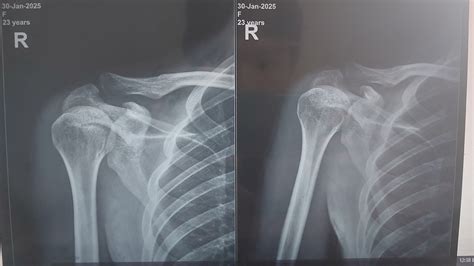

The shoulder is a complex joint involving multiple bones, ligaments, and tendons. To classify a scan as a Normal Shoulder Xray, a radiologist must observe clear, distinct features that indicate the absence of fractures, dislocations, or degenerative bone diseases. The shoulder is primarily a ball-and-socket joint, technically known as the glenohumeral joint.

On a standard radiograph, the primary structures evaluated include:

• The Humerus: Specifically the humeral head, which is the “ball” of the joint. It should appear smooth and rounded.

• The Glenoid: The “socket” part of the scapula (shoulder blade). In a healthy scan, the space between the humeral head and the glenoid should be uniform.

• The Acromion and Coracoid Processes: Bony projections of the scapula that serve as anchor points for ligaments and muscles.

• The Clavicle: The collarbone, which connects to the acromion at the acromioclavicular (AC) joint.

Key Metrics in a Healthy Radiograph

A radiologist checks for specific spatial relationships to ensure everything is aligned. If these metrics fall outside of standard ranges, it often signals an impingement, a dislocation, or arthritis.

Anatomical Landmark Expected Appearance in Normal Scan

Glenohumeral Joint Space Clear, uniform spacing (2-5mm) indicating healthy cartilage.

AC Joint Well-aligned, minimal gap between clavicle and acromion.

Humeral Head Contour Smooth cortical margins without signs of cysts or erosions.

Bone Density Consistent density throughout; no "moth-eaten" appearance.